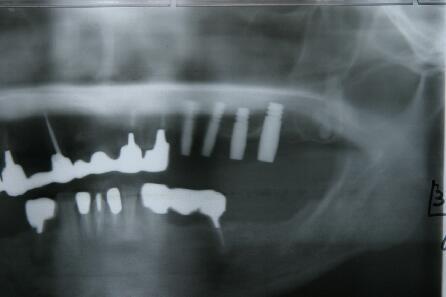

インプラント埋入手術直後のエックス線写真

・骨が薄いので埋入手術後4本のインプラント体をスーパーボンドで固定

・再結晶化HAコーティング施されたインプラント フィクスチャーを使用したため自家骨の移植や 人工骨の添加を行わないで直接埋入